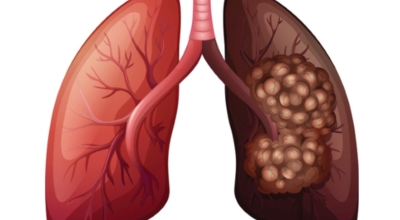

폐암은 폐에 생긴 악성 종양입니다. 폐 자체에 나타나는 원발성 폐암과 다른 장기에서 전이되어 온 전이성 폐암이 있습니다. 전 세계적으로 해마다 130만 명이나 되는 사람들이 폐암으로 사망하는데 이는 암에 의하여 사망하는 것 중에 가장 높은 비중을 차지하고 있습니다.

폐암 초기증상으로는 가슴통증이 있습니다. 폐암 환자들의 약 1/3 환자들이 흉통을 호소해요. 흉통이 발생하는 이유로는 폐의 가장자리 부분에 종양이 생기고 그 종양이 암세포를 생성하면서 흉벽과 흉막에 안착해서 통증을 일으키기 때문입니다.